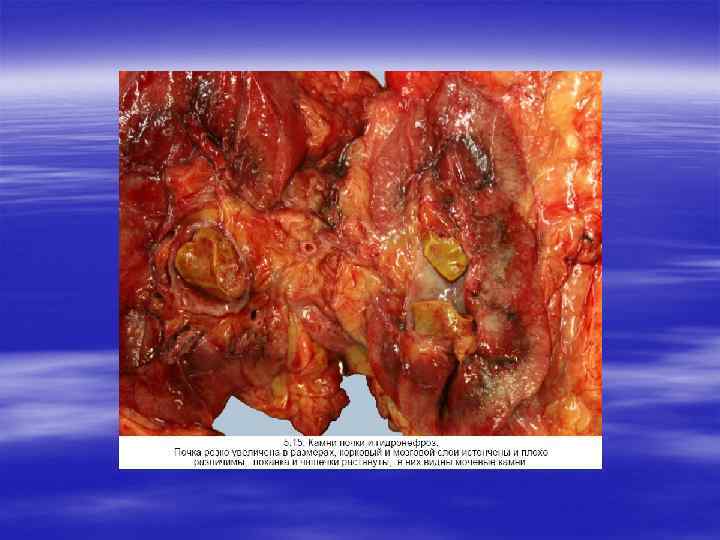

МОЧЕКАМЕННАЯ БОЛЕЗНЬ § Уролитиаз — это хроническое заболевание, сопровождающееся образованием камней на любом уровне мочевыделительной системы, начиная от мочевых канальцев до мочевого пузыря (литогенез). Чаще всего камни образуются в почках, причем в 1 % случаев они могут быть секционной находкой.

§ По величине, структуре и химическому составу они разнообразны: это могут быть фосфаты, ураты, оксалаты, карбонаты, белковые и цистиновые камни. Однако чаще (у 75 % больных) встречаются оксалатные и фосфатные. Органическим матриксом камней являются мукопротеиды, составляющие около 3 % от общей их массы.

Этиология и патогенез. § Одним из важных факторов литогенеза является увеличение в крови концентрации солей, участвующих в образовании камней (солей кальция, фосфорнокислых солей и др. ). § В образовании камней имеют значение также: § характер питания (преобладание углеводов и животных белков); § авитаминоз А, при котором наблюдаемая десквамация метаплазированного эпителия создает предпосылки для формиро вания камней; § трофические и моторные нарушения функции чашечек, лоханок и мочеточников, что способствует застою мочи; § воспалительные процессы в мочевых путях. В последнем случае установлена роль инфекции мочевыводящих путей в образо вании магнезий аммониево фосфатных камней, особенно при инфекциях, возбудителями которых являются протей вульгарный и стафилококк; § изменения реакции мочи в сторону повышения кислотности или щелочности; § избыточная секреция мукопротеидов, которые формируют органический матрикс камней. § Патологическая анатомия.

ГИДРОНЕФРОЗ § Гидронефроз представляет собой дилатацию почечной лоханки и чашечек, сопровождающуюся атрофией паренхимы. Основная причина гидронефроза — это обструкция мочевыводящих путей на любом уровне от уретры до почечной лоханки. Обструкция может быть внезапной или развиваться исподволь, врожденной или приобретенной, полной или частичной.